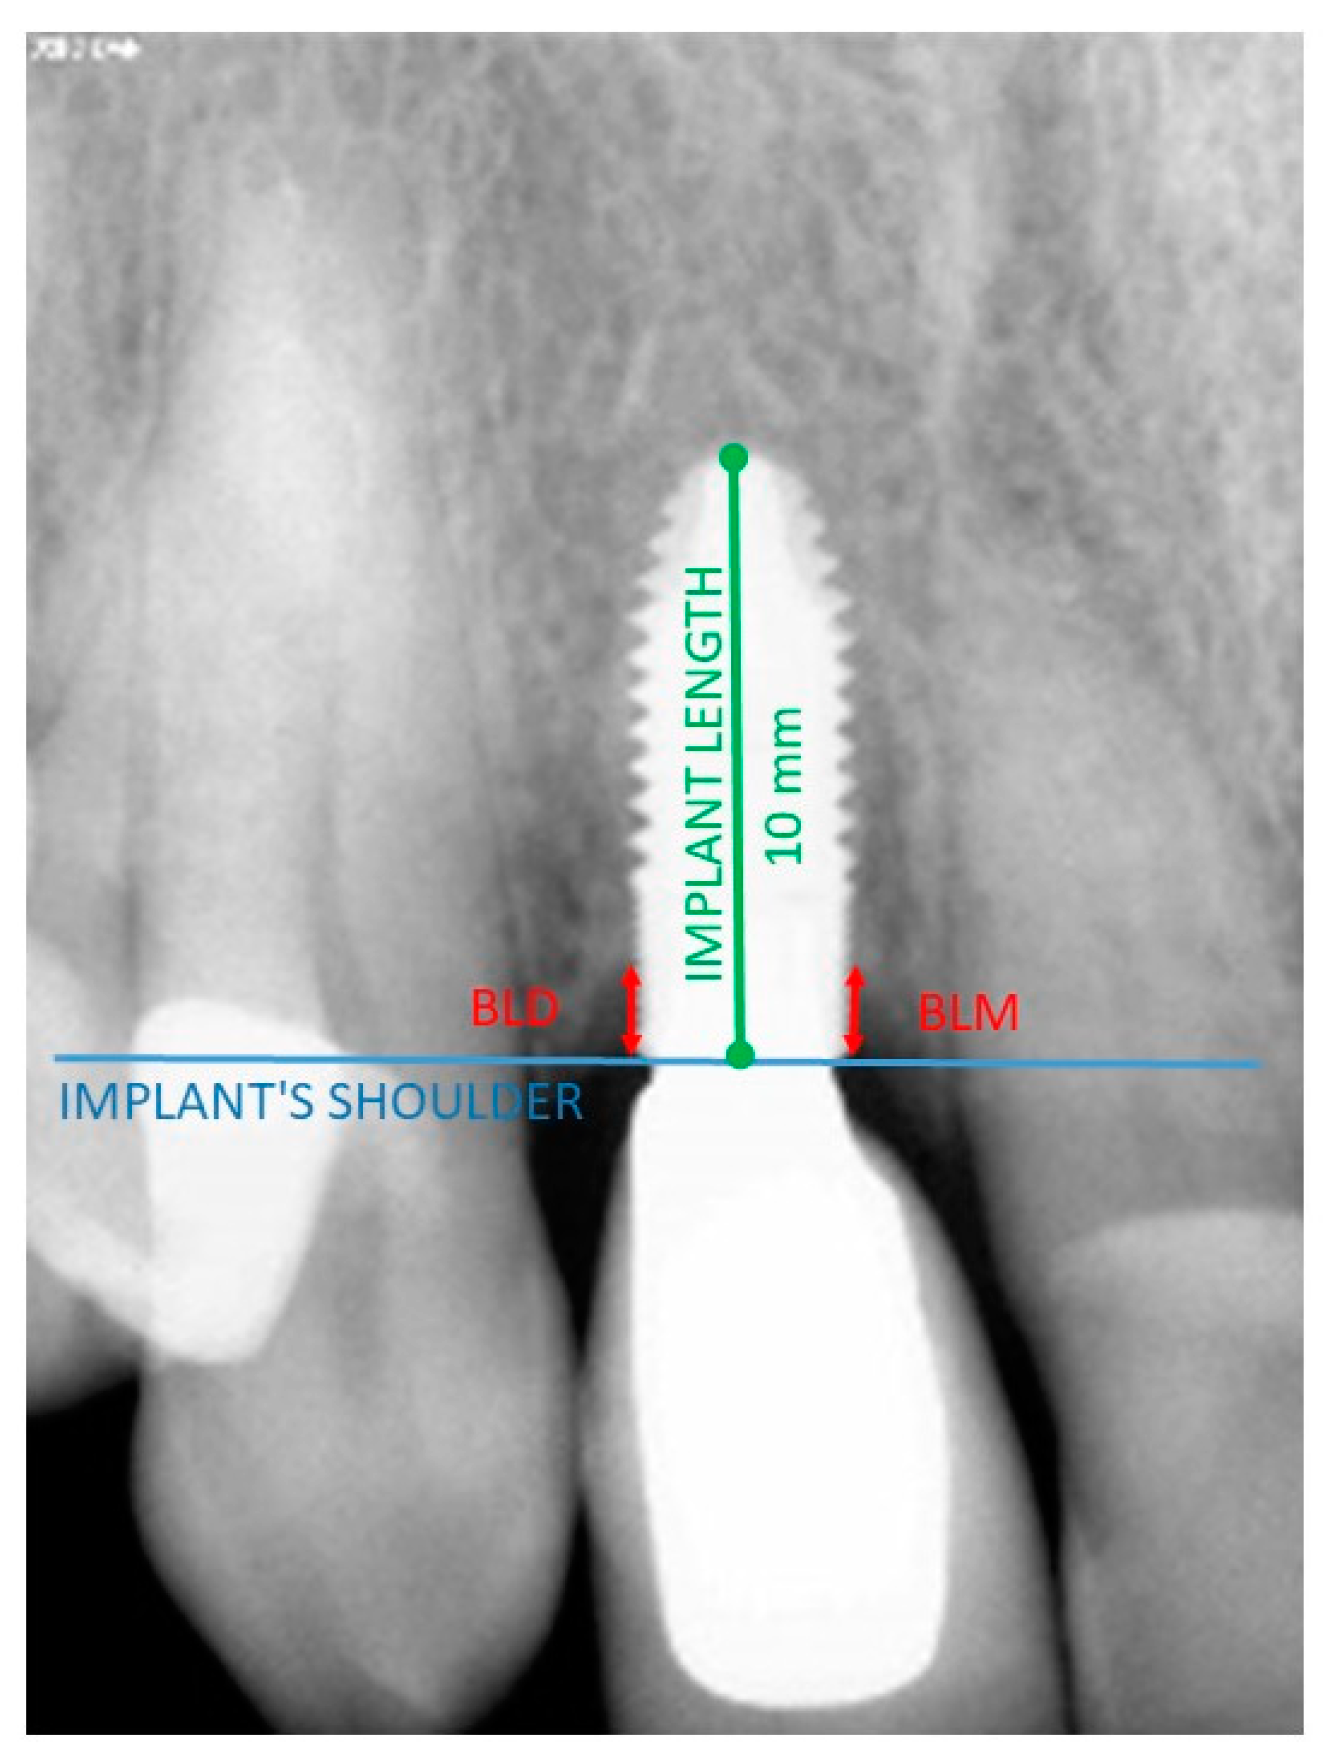

The evaluation was performed using ImageJ software (the U.S. National Institutes of Health, Bethesda, MD, USA) once the images had been calibrated. The B.L. was measured from the neck of the implant to the first contact between the bone and the implant, both mesially and distally. All measurements were taken in mm. The mean of both measurements was taken as the B.L. measurement of the implant. These measurements were taken both at the time of prosthesis placement and after 5 years for both types of implants (Figure 2).

Figure 2.

Measurements taken to determine the bone level (BL). Calibration of the program based on implant length and diameter. BLM = mesial bone level, BLD = distal bone level. The B.L. for a given implant and time was calculated as the mean of both measurements (BLM + BLD/2).